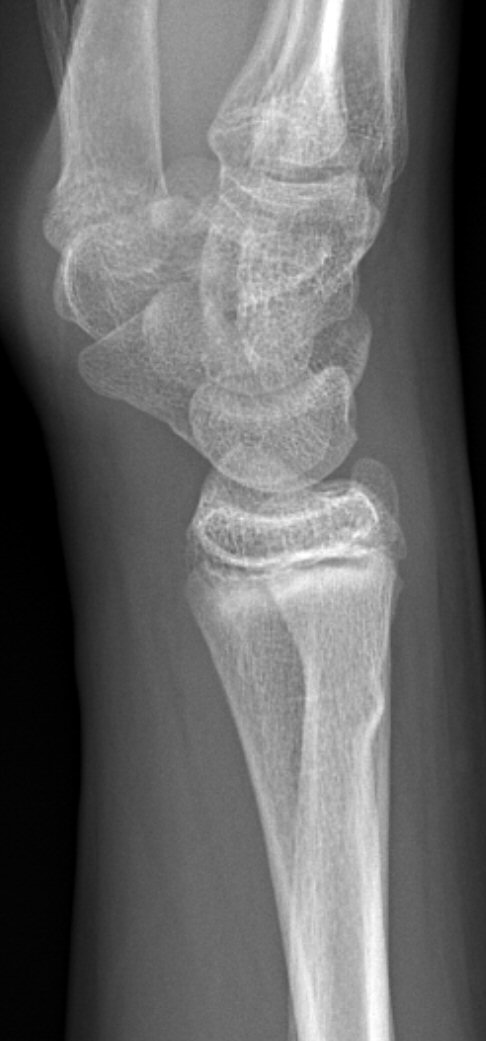

Dorsalbockad distal radiusfyseolys Salter-Harris typ 2 före och efter reposition